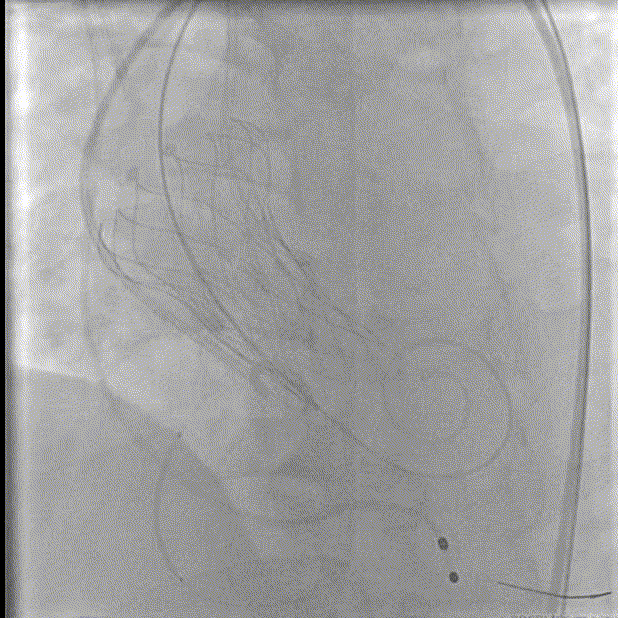

术后造影

入路造影

术后评估

术后超声显示:释放后瓣膜位置形态良好,瓣叶活动可,患者的跨瓣压差由术前的60mm/Hg改善至术后的6mm/Hg,术后患者血流动力学得到明显改善,获益明显。